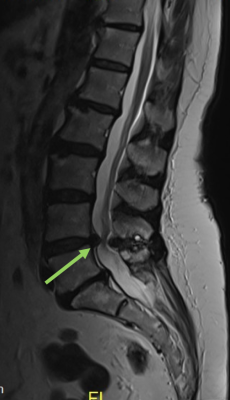

Zervikaler/Lumbaler Bandscheibenvorfall

Im Rahmen degenerativer Verschleißprozesse der Bandscheibe kann es zum Austritt von Bandscheibengewebe in den Wirbelkanal kommen. Durch Bedrängung der dort verlaufenden Nerven kommt es abhängig von der Schädigungshöhe zu Schmerzen, Taubheitsgefühl und Lähmungserscheinungen im Bereich der Arme bzw. Beine. Wird das Rückenmark selbst durch den Druck der Bandscheibe geschädigt, so können Blasen-Mastdarmstörungen oder gar eine Querschnittlähmung auftreten.

Im Normalfall kann der lumbale Bandscheibenvorfall minimalinvasiv mit Hilfe des Mikroskops entfernt werden, ohne dass eine Stabilisierung der Wirbelsäule notwendig ist.